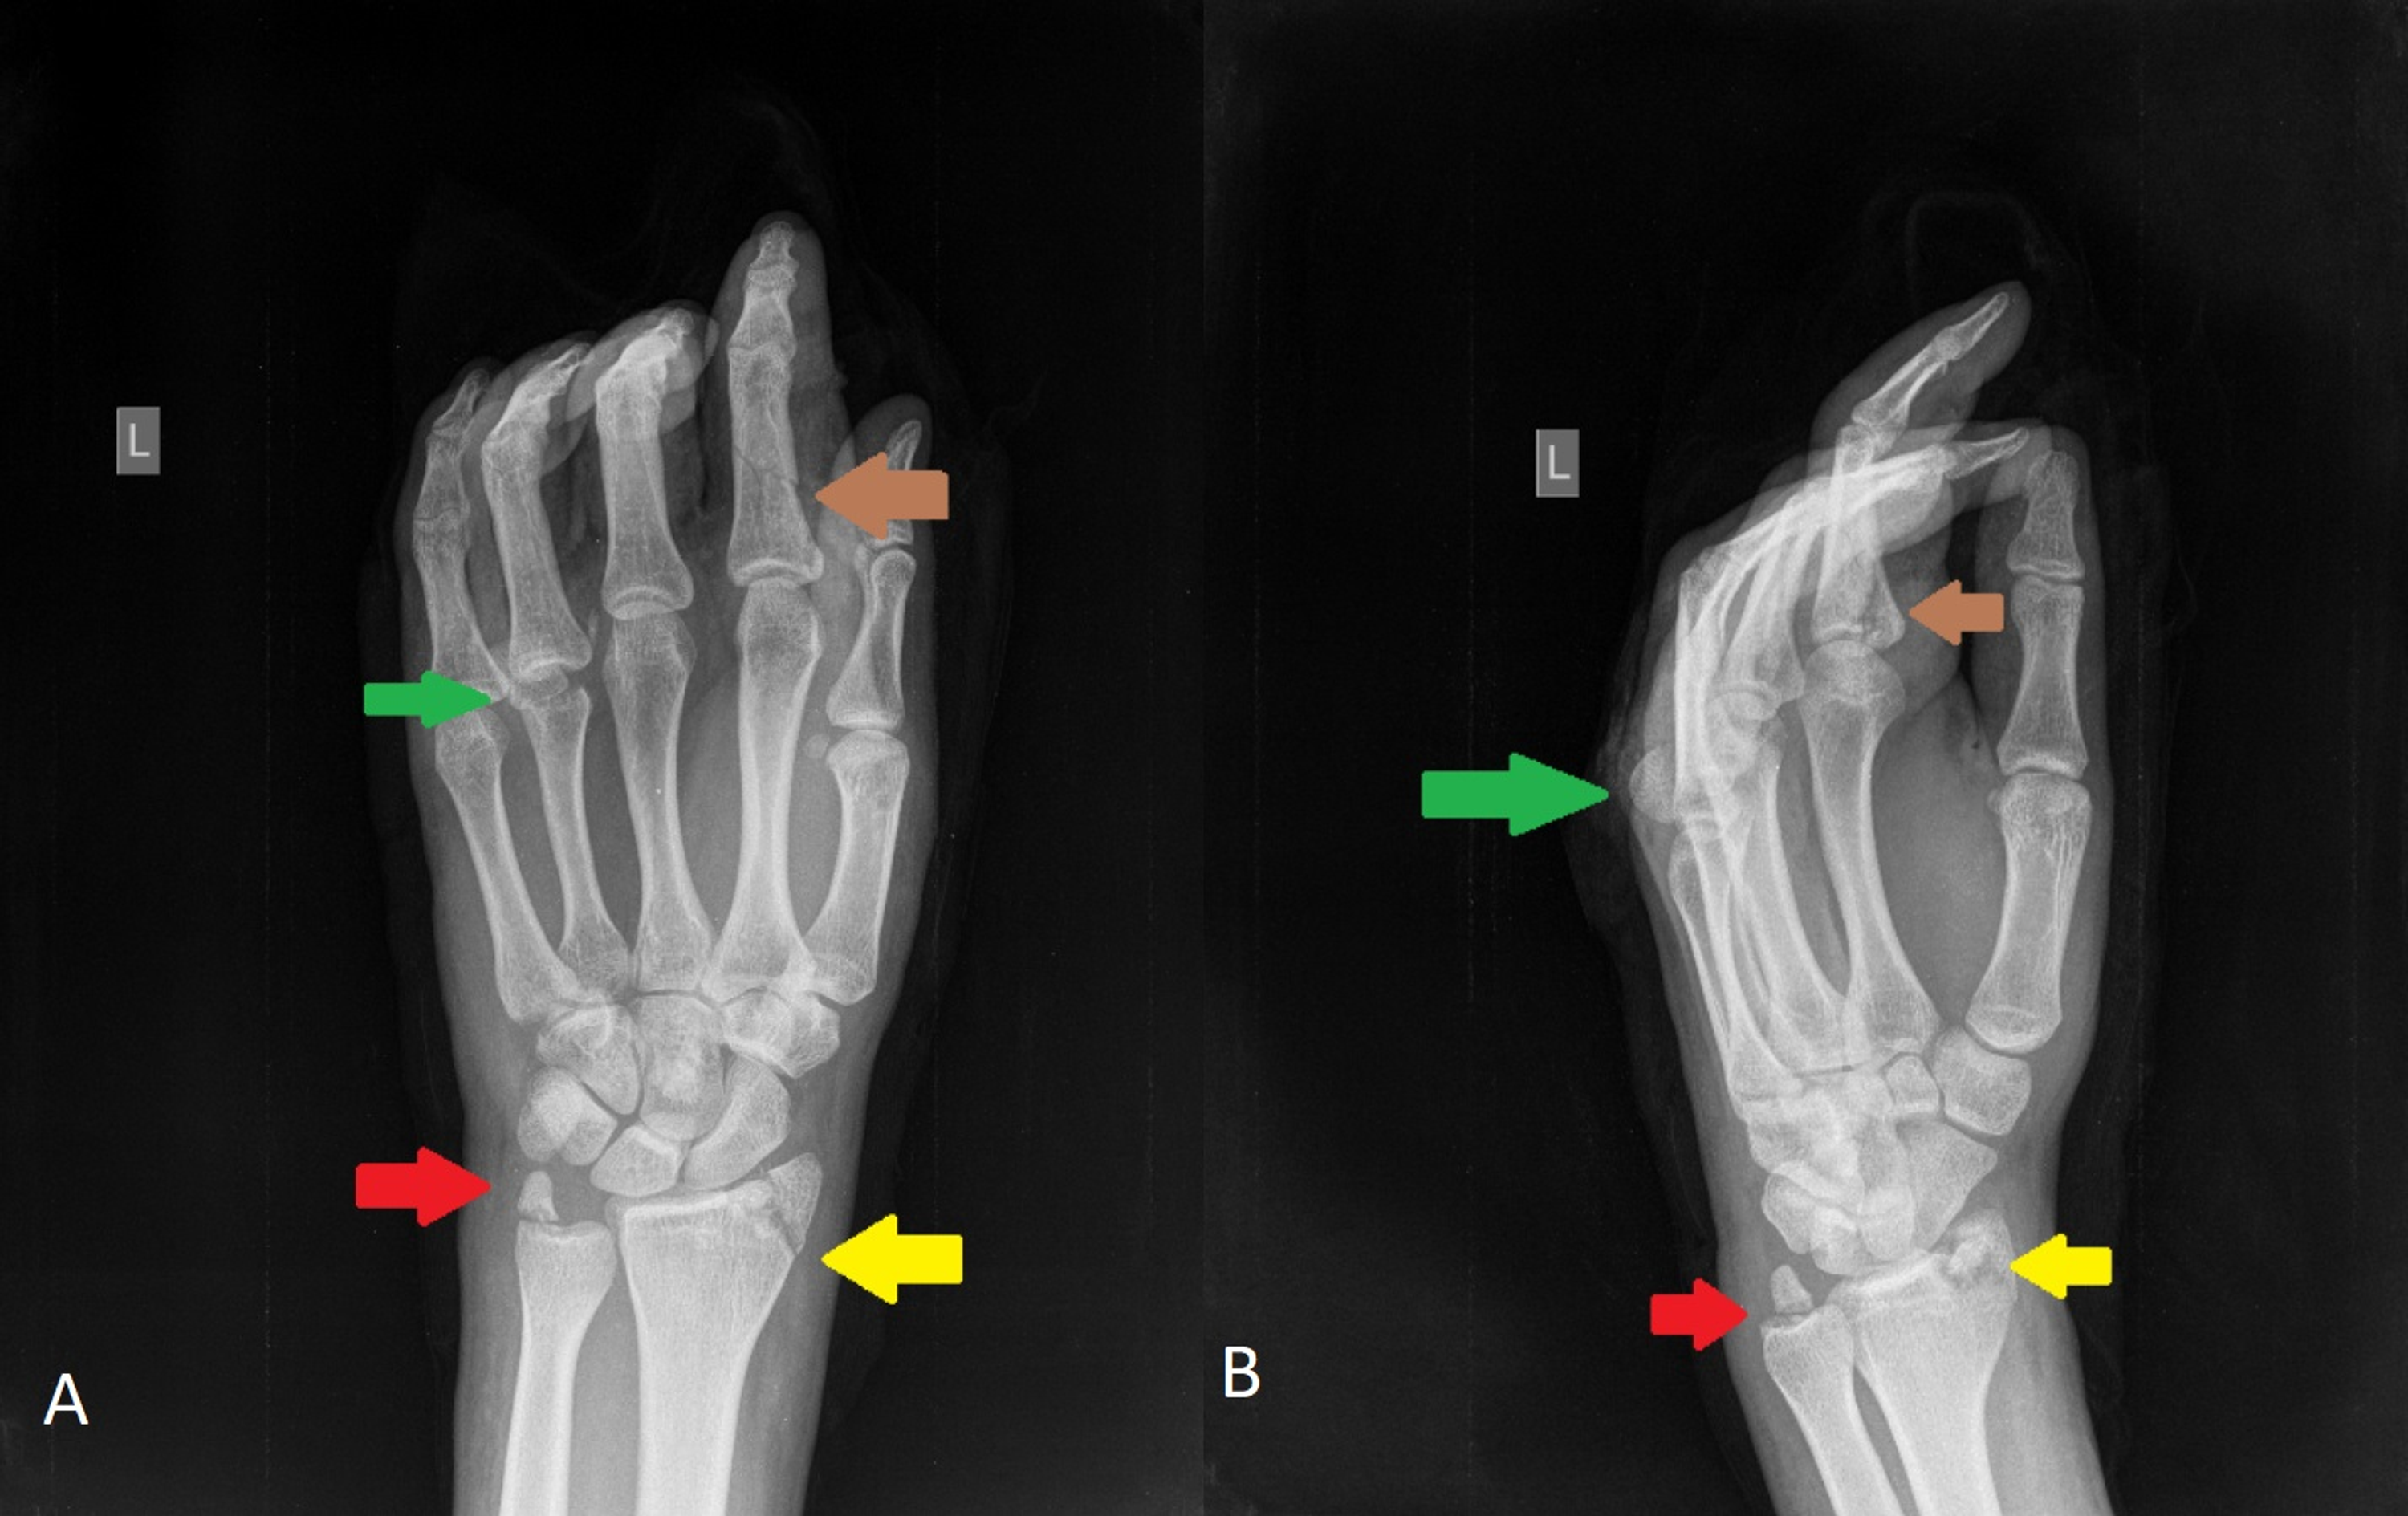

Ulnar Styloid Fracture X Ray Hairline Fracture Ulna X Ray Ct or mri may be. Distal radial fractures are a heterogeneous group of fractures that occur at the distal radius and are the dominant fracture type at. Radius and ulnar shaft fractures, also known as adult both bone forearm fractures, are common fractures of the forearm caused by either direct trauma or indirect trauma (fall). People may experience fractures in. Hairline Fracture Ulna X Ray.

From www.clinicaladvisor.com

OrthoDx Isolated Ulnar Styloid Fracture Clinical Advisor Hairline Fracture Ulna X Ray People may experience fractures in one or both bones after a fall. Radius and ulnar shaft fractures, also known as adult both bone forearm fractures, are common fractures of the forearm caused by either direct trauma or indirect trauma (fall). A forearm fracture can occur in one or both of the forearm bones. X rays are the gold standard for. Hairline Fracture Ulna X Ray.

From mavink.com

Ulnar Styloid Fracture X Ray Hairline Fracture Ulna X Ray X rays are the gold standard for diagnosing forearm fractures and must include views not only of the forearm, but the wrist and elbow as well to exclude concomitant injuries. Distal radial fractures are a heterogeneous group of fractures that occur at the distal radius and are the dominant fracture type at. Radius and ulnar shaft fractures, also known as. Hairline Fracture Ulna X Ray.